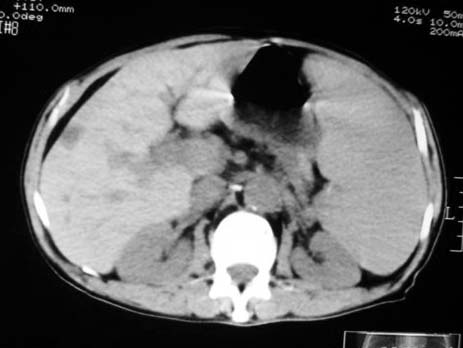

以下是引用dyqct在2007-4-20 16:38:00的发言:[br]考虑:1、巨脾;[br] 2、肝内多发低密度,首先考虑转移瘤;[br] 3、胆囊多发结石。